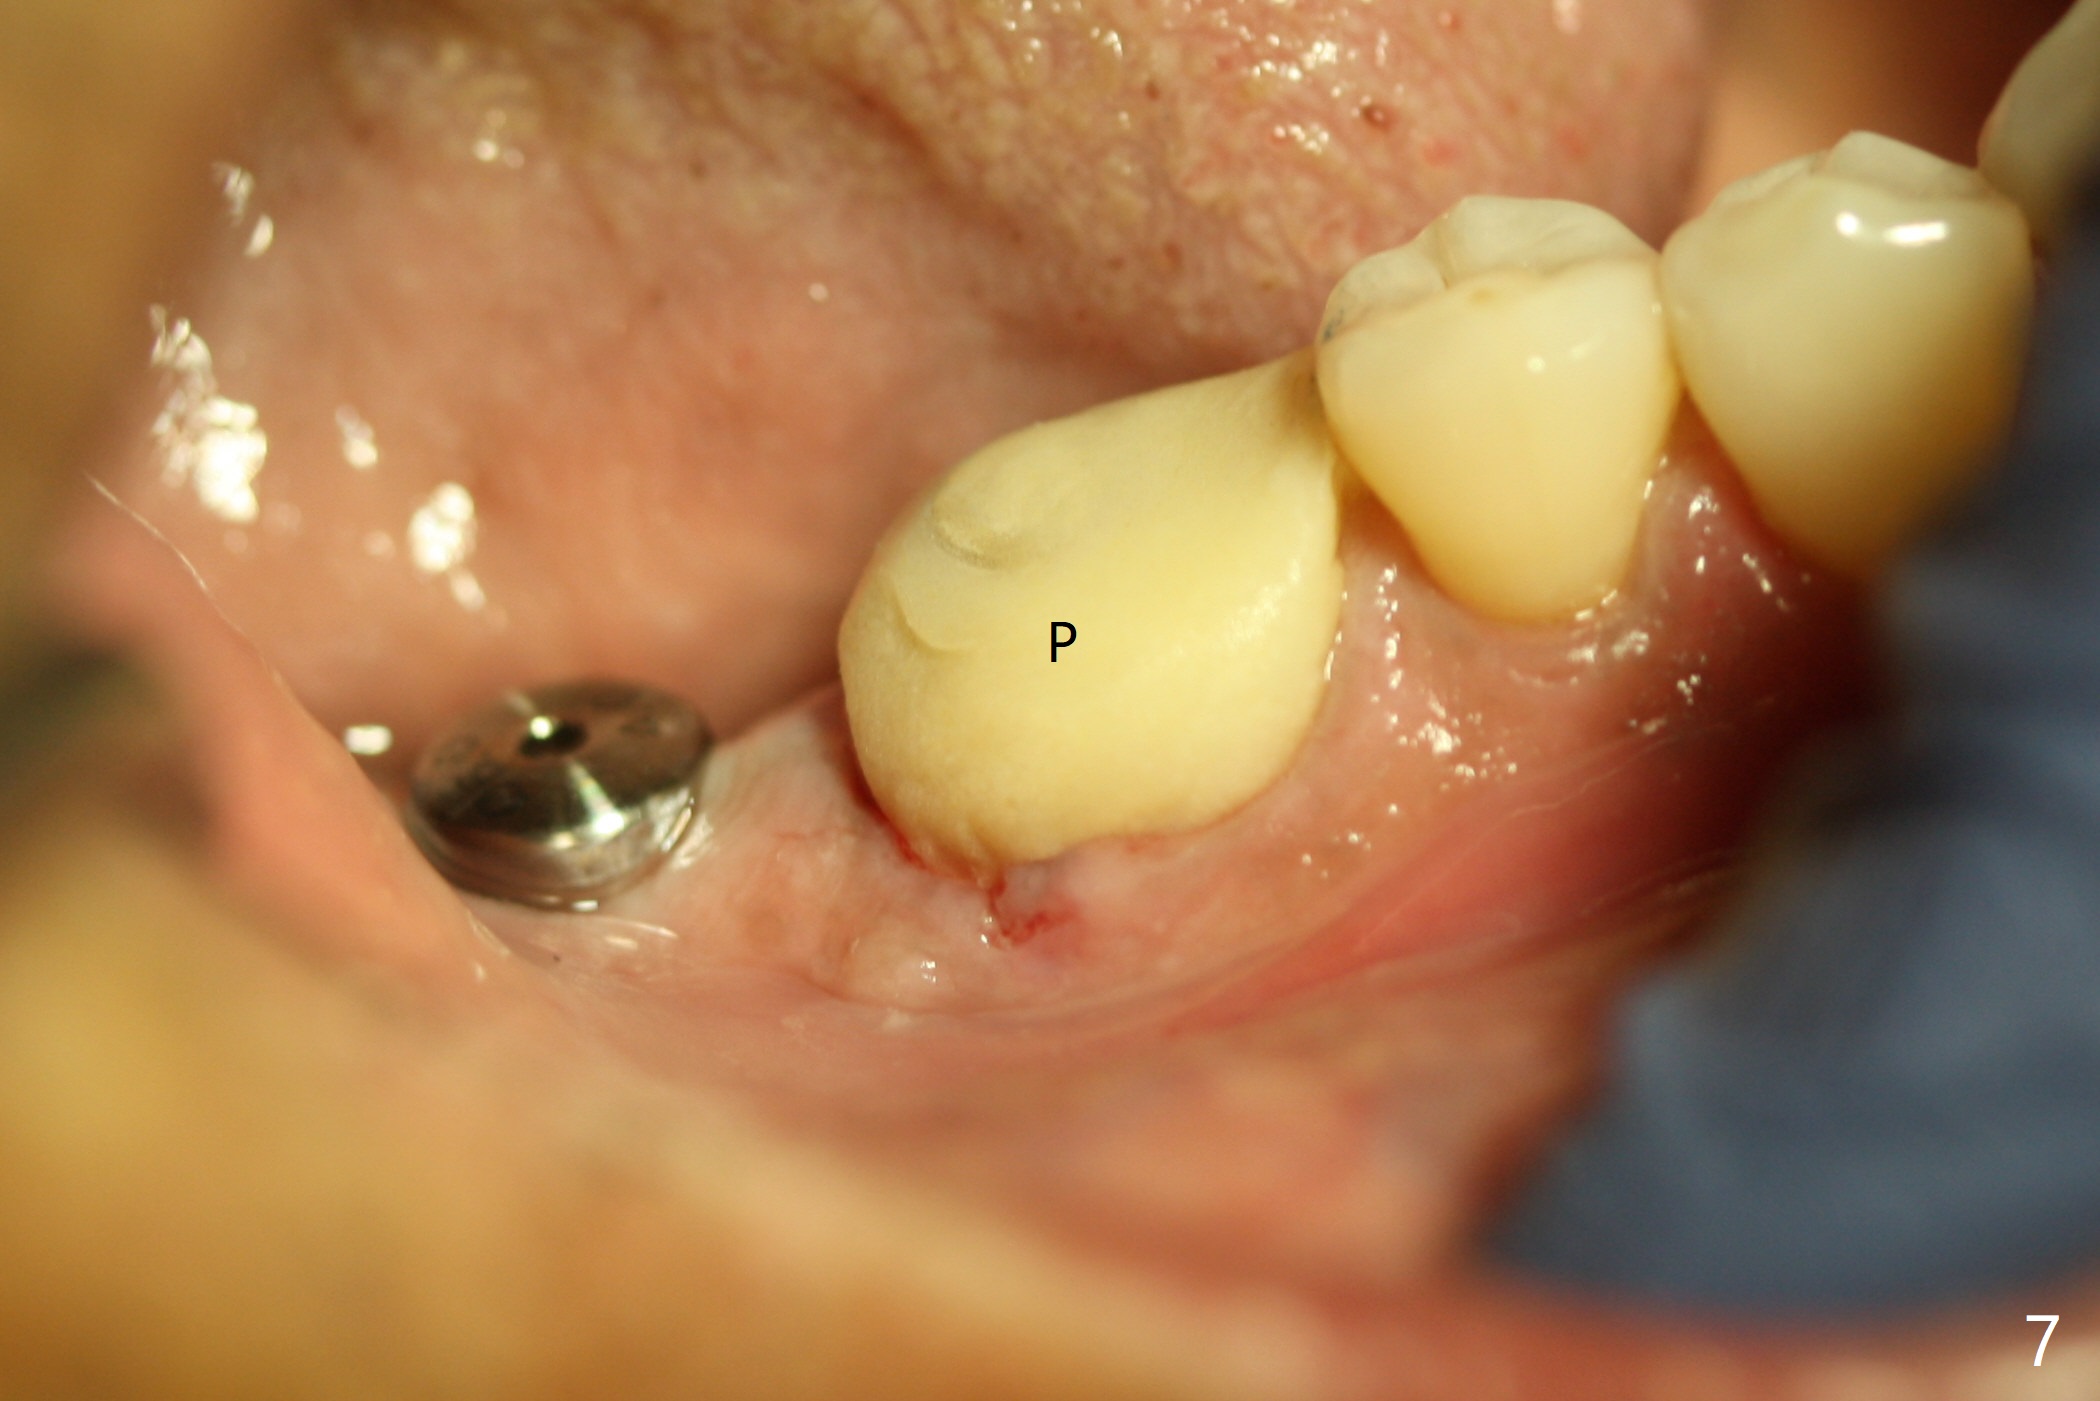

Abutment vs. Definitive One

After extraction of the tooth #30 with lingual subgingival fracture (Fig.1), the septum is fairly large (Fig.2 S). A bony vertical anchor pin (Fig.3 *) is inserted in the septum following pointed drill to to stabilize the guide during osteotomy and implant placement of #31. When the latter is finished, a fixture anchor pin is used at #31 as planned. A healing abutment is placed at #31 because of supraeruption of the tooth #2 (Fig.4,5), while a cementation abutment is placed at #30 (Fig.5) with autogenous bone (from drills) and allograft placed around it (*, Fig.6). Finally an immediate nonfunctional provisional is fabricated to keep the bone graft in place (Fig.7 P). The bone graft remains in place gel-like nearly 1 month postop (Fig.8). CBCT axial section shows that there is not enough space for mini implant placement at the tooth #2 (Fig.9). Restoration-induced intrusion will be conducted using the implants at #30 and 31 three-4 months postop. The buccal gingiva (Fig.10 *) is lingual to the provisional (P) nearly 1.5 months postop. When the provisional is removed, it appears that the mesiobuccal bone graft has lost (Fig.11). Two days later, the cementation abutment is loose and removed; the gingival cuff looks healthy (Fig.12). A 6.8x5 mm healing abutment is placed (Fig.13). In 2.5 to 3 months, abutments will be placed at #30 and 31. Splinted provisional will be fabricated over supraocclusion to intrude the tooth #2 with a stop on the left side. Surprisingly the patient agrees to intrude the tooth #2 with 2 mini implants 5.5 months postop (Fig.14,15). However, the miniimplants dislodged. Due to coronavirus, the implants are restored with heavy abutment and opposing tooth trimming 1 year 9 months postop (Fig.16). Magicore should have been placed instead.